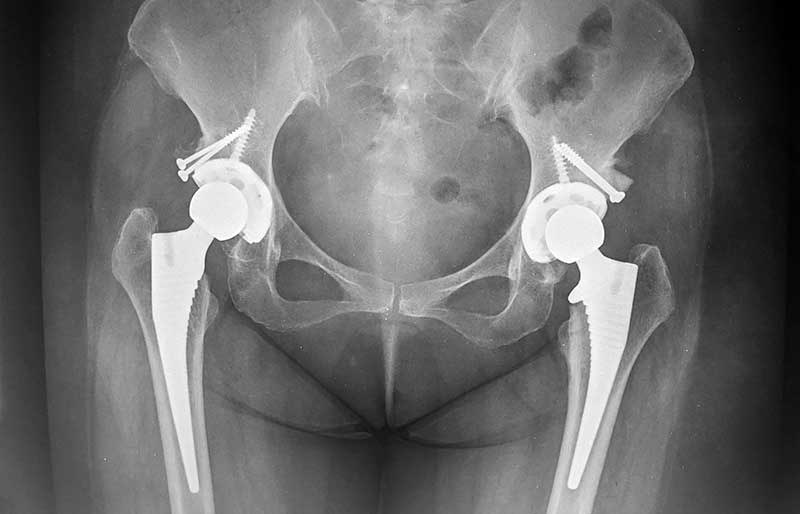

Operasi penggantian sendi panggul adalah suatu operasi untuk mengganti sendi panggul yang rusak dengan sendi buatan yang disebut prosthesis. Penyebab utama kerusakan sendi panggul adalah osteoartritis (baca penjelasan tentang “Osteoartritis”) dan sendi panggul adalah sendi terbanyak kedua setelah lutut yang terserang penyakit ini.

Operasi penggantian sendi panggul merupakan pengobatan terbaik untuk osteoartritis panggul stadium yang berat. Ada empat tujuan operasi ini, yaitu menghilangkan rasa sakit sendi yang telah rusak, memperbaiki lingkup gerak sendi yang sebelumnya kaku dan terbatas, mengembalikan kemampuan penderita melakukan aktivitas harian tanpa rasa sakit, dan meningkatkan kualitas hidup sehingga penderita kerusakan sendi dapat menjalani hidup secara aktif bebas dari nyeri sendi panggul.